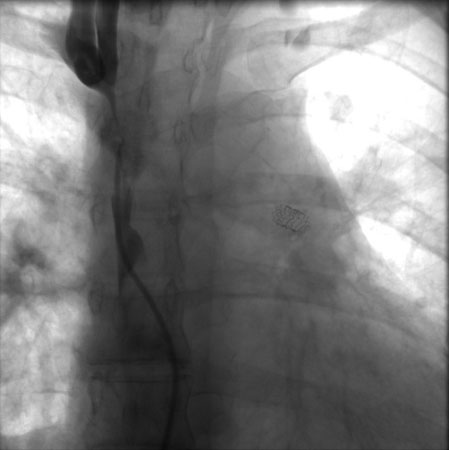

If a patient presently acutely with airway obstruction, the airway must be secured initially via intubation or surgical methods. After the patient has been stabilized, radiotherapy and corticosteroids should be considered. Urgent treatment with radiotherapy and corticosteroids should only be used for life-threatening situations and should be deferred otherwise due to interference with subsequent histopathological diagnosis. A useful procedure for patients with severe SVCS in respiratory distress is endovascular therapy with stenting; meta-analysis show it has high technical and clinical success rates. It is done via the femoral vein and performed under conscious sedation; fluoroscopic guidance and iodinated contrast are used alongside heparin. The image below shows SVC stenosis with stent placement in the left pulmonary artery.